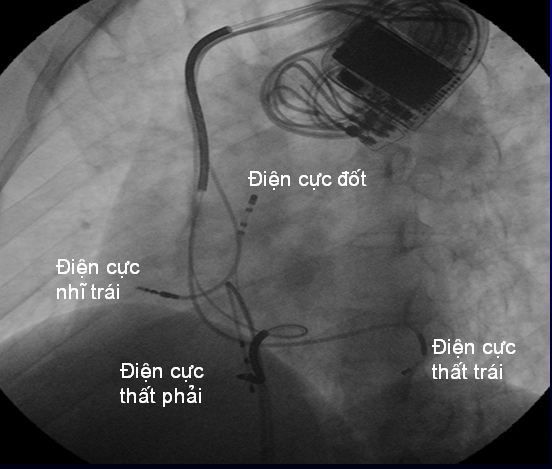

Bệnh nhân không phải nhập viện đến tháng thứ 6 sau cấy máy. Khi khám lại vào tháng thứ 6, bệnh nhân có cải thiện với độ NYHA I. Siêu âm tim Dd = 55 cm và EF = 48%. Trên máy chương trình ghi lại bệnh nhân vẫn còn rất nhiều đoạn tim nhanh thất. Bệnh nhân sau 2 tuần khi kiểm tra lại vào tháng thứ 6, đã phải nhập viện trở lại vì có nhiều nhát đánh sốc liên tục. Máy chương trình cho thấy có nhiều tim nhanh thất. Hình ảnh điện tâm đồ cho thấy rối loạn nhịp thất từ đường ra thất phải (hình 1). Bệnh nhân đã được tiến hành thăm dò điện sinh lý và triệt bỏ tim nhanh thất (hình 2).

Hình 2. Hình ảnh triệt bỏ ổ loạn nhịp bằng sóng radio qua đường ống thông ở ca lâm sàng số 3.